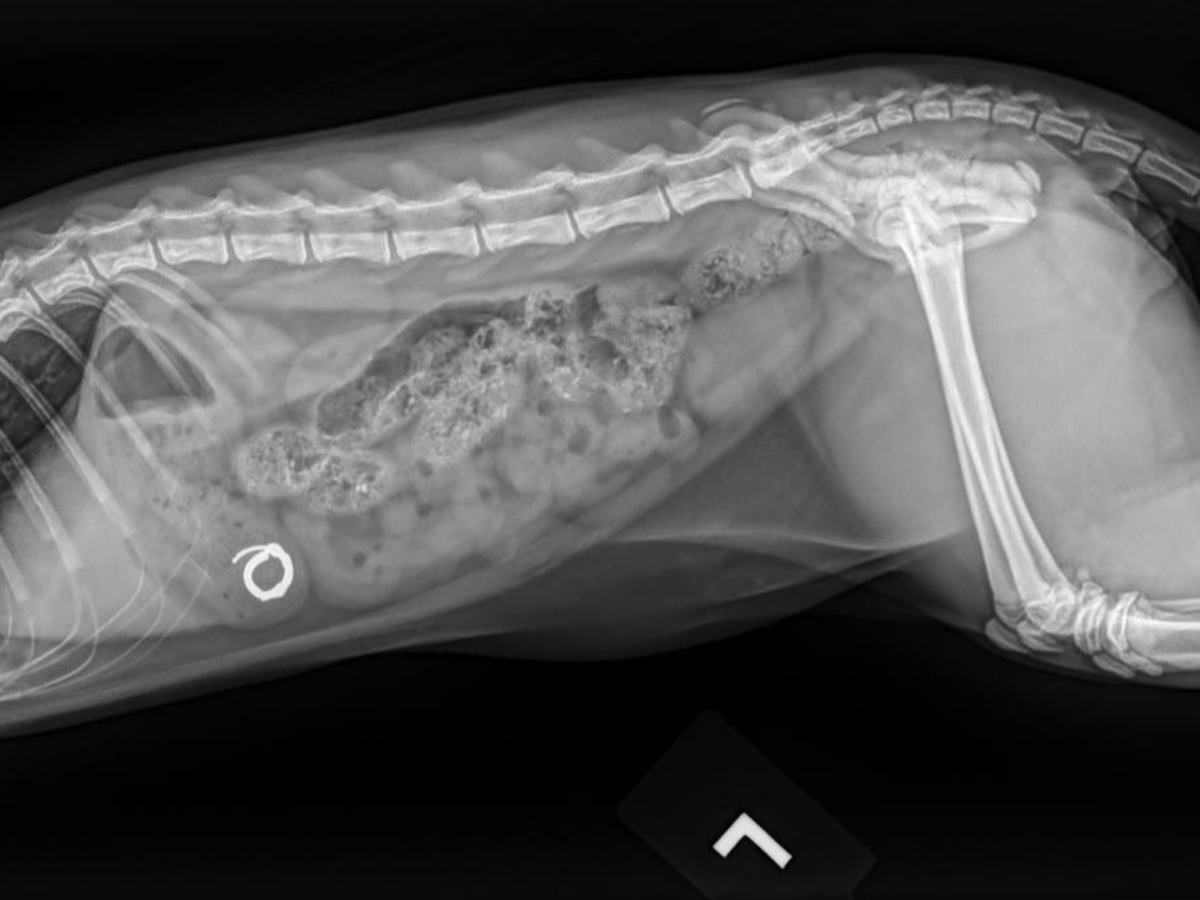

On the night of Sunday, August 17th, Smudge was cuddling with us in bed before we went to sleep. He started licking Chelsea's ear, and before she knew what had happened, he had somehow dislodged her hoop earring and swallowed it straight down his throat. After frantically checking the area around our bed and sifting through his poops the next morning, we took him to urgent care to get radiographs, and the results confirmed the worst. He had swallowed the whole earring, and it was currently resting in his stomach.